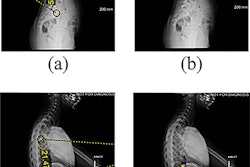

The lower extremity measurement pipeline is illustrated using a representative slot-scanning radiograph. The AI model was trained to segment the femur and tibia: (A) the original radiograph and (B) the same radiograph showing the segmentations (boxes) produced by the model. (C) The segmentations in B were used by the model to identify the top of the femoral head, medial tibial condyle, and tibial plafond (lines). These locations were used by the model to measure the length of the femur, tibia, and lower extremity overall. Image courtesy of Radiology.

The lower extremity measurement pipeline is illustrated using a representative slot-scanning radiograph. The AI model was trained to segment the femur and tibia: (A) the original radiograph and (B) the same radiograph showing the segmentations (boxes) produced by the model. (C) The segmentations in B were used by the model to identify the top of the femoral head, medial tibial condyle, and tibial plafond (lines). These locations were used by the model to measure the length of the femur, tibia, and lower extremity overall. Image courtesy of Radiology.

The CNN model was trained to segment the femur and tibia on the x-rays and measure total leg, femoral, and tibial length, with results showing the model’s mean absolute error measurements were 0.25 cm for the femur, 0.27 cm for the tibia, and 0.33 cm for composite lower limbs.